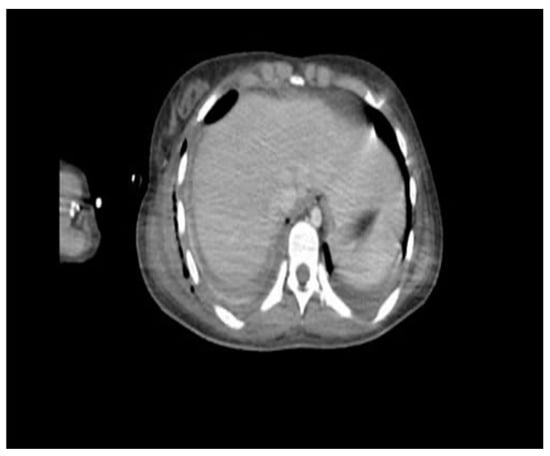

Figure 4. Chest X-ray after surgery (72 h after), with the persistence of multiple alveolar consolidation zones, pleural drainage, and skin drainage.